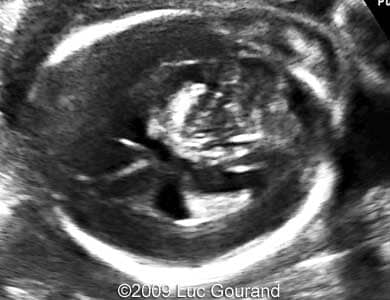

Images 1,2: Image 1 shows an axial plane of the brain, thalami are well separated, cavum septi pellucidi is not seen. Image 2 shows the confluence of the posterior horns of the lateral ventricles.

Case262_1

Case262_2

Images 3,4: Image 3 shows the confluence of the posterior horns of the lateral ventricles. Image 4 shows the absence of corpus callosum, the arrows indicate a wavy hypoechogenic structure in the mid-line, which could be detected on the MRI as well (see Image 7).

Case262_6

Case262_5